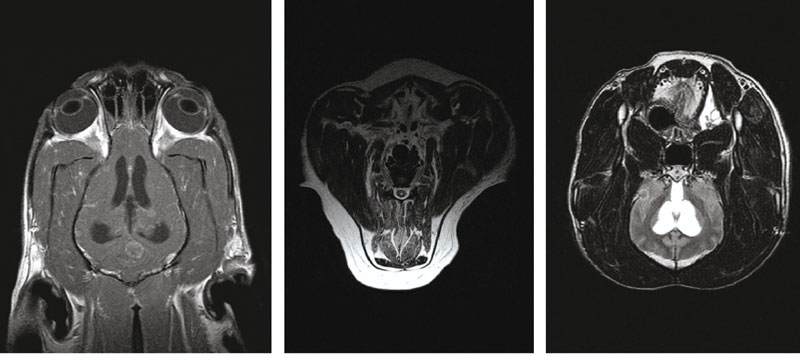

МРТ-АМИКО — медицинское оборудование, разработанное на основе технологии постоянного магнита. Оно отличается экономичностью, компактностью, низкими затратами на обслуживание и высокой диагностической точностью, что особенно важно для ветеринарной медицины.

Технологии активного экранирования контура, а также шиммирования высокого порядка и быстропоточная конструкция эффективности полюсов обеспечивают эффективность исследования и получение снимков высокого качества.